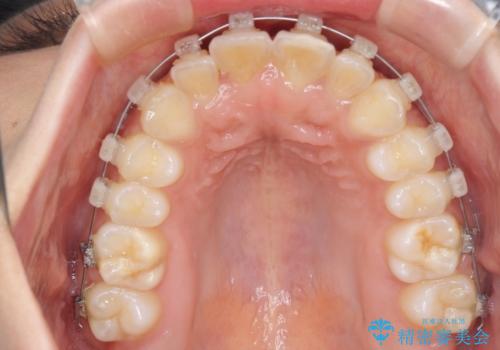

- クリアブラケット

ワイヤーでもマウスピースでも治療可能でしたが、自己管理の重要なマウスピース矯正は自分には向かないとのことで、ワイヤー矯正で治療することとしました。

大きなトラブルもなく、順調に歯列が整ったため、僅か9ヶ月で装置を外すことができました。

あまりに短期間であったため、患者様自身も非常に驚いていらっしゃいました。